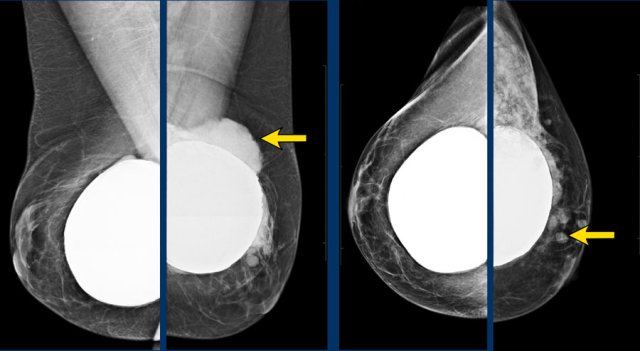

Mammography

Same patient before and after prepectoral breast augmentation.

Especially prepectoral implants can reduce mammographic assessment.

Still

mammography and 3D tomosynthesis can be well performed and in fact has the highest

PPV for recognition of extra capsular silicone.

It also objectively detects changes

in time, shows calcifications, can show surrounding fluid shadow and of course adds

important findings in fibroglandular tissue.

Typical appearance of silicone outside of the capsule presenting as dense well deliniated masses outside the contour of the breast implant.